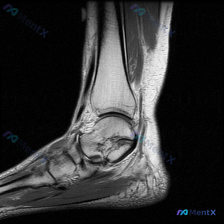

今天整理了一例踝关节MRI T2加权轴位影像的读片分析,分享一下整个思路过程。 一、影像基础信息 这是一张踝关节T2加权轴位MRI,扫描层面位于胫距关节下方,可见距骨体,图像质量清晰,无明显运动伪影。 二、影像所见整理 1. 骨结构:距骨体内侧缘可见片状明确T2高信号,提示骨髓水肿/骨挫伤;胫距关节...